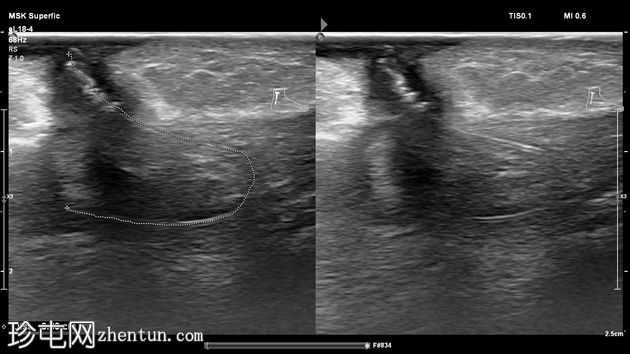

超声检查

斜位

纵位

左足跟皮下组织内可见一管状高回声物质,呈串珠状,与手术缝线相符,周围环绕着低回声积液。与缝线相连的是一根细细的、呈轨道状的高回声合成单丝,它穿过跟腱呈弧形走行,该缝线为不可吸收缝线。